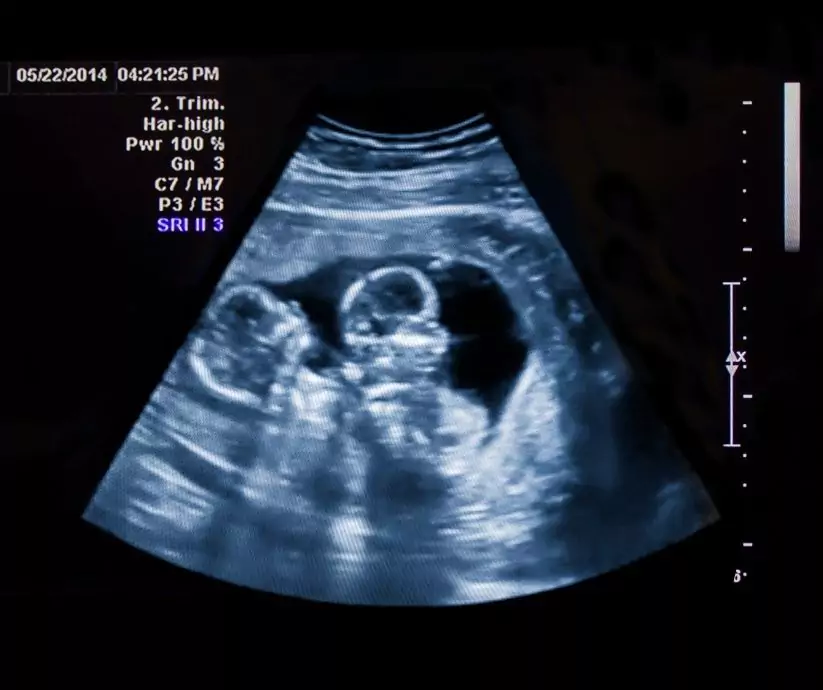

Bliźnięta – Poród naturalny czy cięcie cesarskie? Oto jest pytanie. Każda ciąża bliźniacza to podwójna radość, ale także zwiększony wysiłek dla organizmu mamy oraz możliwość wystąpienia nieprawidłowości w rozwoju dzieci, dlatego nazywamy ją ciążą podwyższonego ryzyka. Często także ciąże bliźniacze są rozwiązywane drogą cięcia cesarskiego. Dzieje się tak, jeśli poród rozpoczyna się przedwcześnie (co zdarza się praktycznie zawsze), jedno z bliźniąt jest nieprawidłowo położone w macicy (czyli inaczej niż główkowo) bądź występują inne czynniki ryzyka dla mamy lub dzieci. Dlatego tym razem opowiem Ci wszystko, co powinnaś wiedzieć o porodzie w ciąży bliźniaczej – zarówno tym w sposób naturalny, jak również przez cięcie cesarskie. Przyjrzymy się bliżej temu w jakich sytuacjach poród siłami natury jest możliwy oraz kiedy wskazana lub niezbędna jest "cesarka". W końcowej fazie artykułu omówimy też jak przebiega poród bliźniaków. Gotowa? Zatem miłej lektury!

"Na wstępie warto zaznaczyć, że ciąża bliźniacza jest ciążą wysokiego ryzyka i powinna być ona prowadzona w specjalistycznym ośrodku. Ciąża ta wymaga szczególnego nadzoru położniczego – częstych badań USG, wykonywania zapisów KTG w zależności od rodzaju ciąży bliźniaczej – czasem nawet od 26. tygodnia ciąży. Poród siłami natury w przypadku ciąży bliźniaczej zależy w dużym stopniu od możliwości zapewnienia bezpieczeństwa matki i dziecka i ma na celu maksymalną redukcję urazów okołoporodowych." – wyjaśnia położna Martyna Zdunek.

Poród w ciąży bliźniaczej jest obecnie jednym z największych wyzwań współczesnego położnictwa. Retrospektywne analizy wskazują wyższe ryzyko powikłań przy porodach drogami natury w porównaniu do elektywnego zakończenia ciąży cięciem cesarskim. Nie potwierdzają jednakże tej zależności niedawno opublikowane wyniki wielośrodkowego badania randomizowanego Twin Birth Study. Badaniem objęto 2804 kobiet w ciążach bliźniaczych pomiędzy 32. a 39. tygodniem ciąży z położeniem główkowym pierwszego płodu. Nie stwierdzono istotnych statystycznie różnic w powikłaniach porodowych i noworodkowych pomiędzy badanymi grupami.